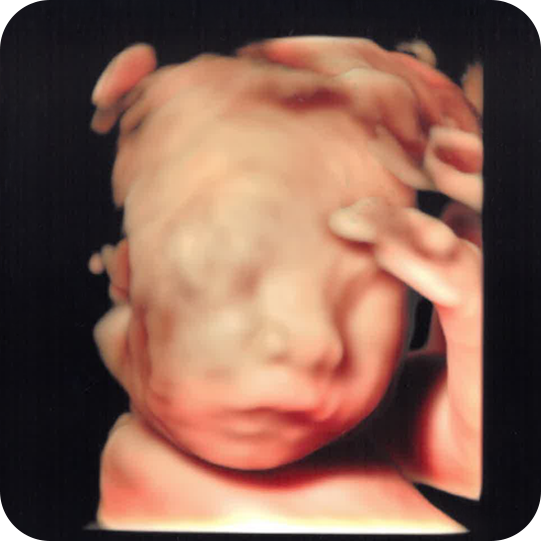

4Dエコー外来では、国内最高峰の最新機種で、赤ちゃんの顔の表情や動きをリアルタイムで確認できます。

タイミングが合えば、あくびや指しゃぶり、笑う瞬間が見れるかもしれません。

25週

26週

27週

32週